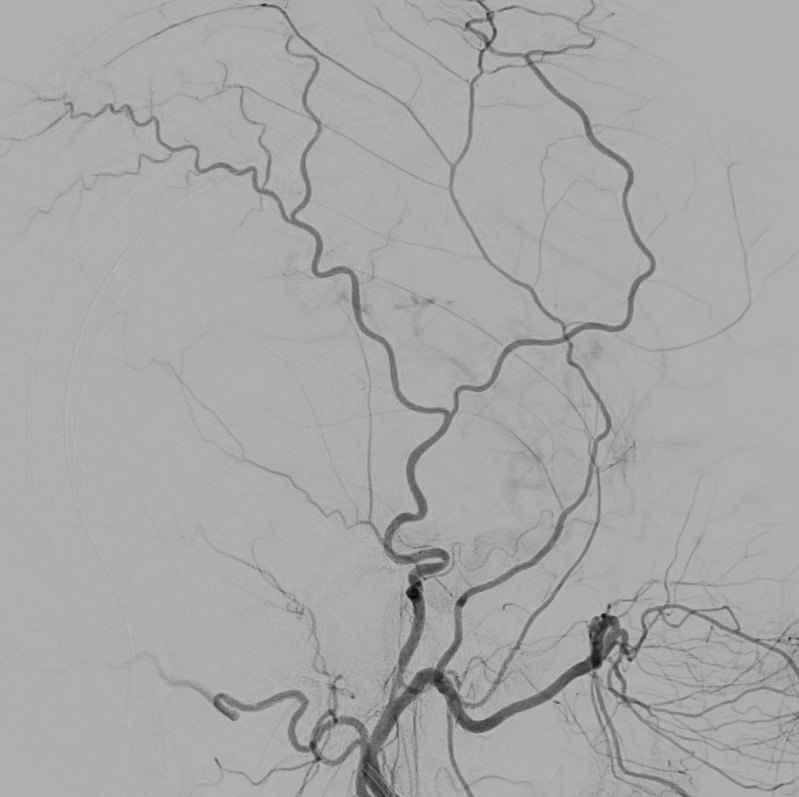

Pre-embolization angiogram